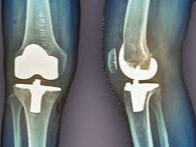

나이가 들면 관절 사이 연골이 점차 닳아 없어지면서 뼈와 뼈가 직접 맞닿아 통증을 유발합니다. 특히 무릎은 체중을 지탱하는 관절로써 손상되기 쉬우며, 다음과 같은 증상이 있다면 인공관절 수술이 필요할 수 있습니다.

이런 경우에는 무릎 인공관절 치환술이 가장 효과적인 치료법으로 여겨지며, 수술 후에는 통증 완화 및 활동 능력 회복이 가능합니다.

일반적으로 무릎 인공관절 치환술은 한쪽 무릎 기준 300만 원에서 500만 원까지 발생할 수 있습니다. 수술 전 검사비, 입원비, 인공관절 재료비, 수술 후 재활치료까지 포함하면 금액은 더 늘어날 수 있습니다.